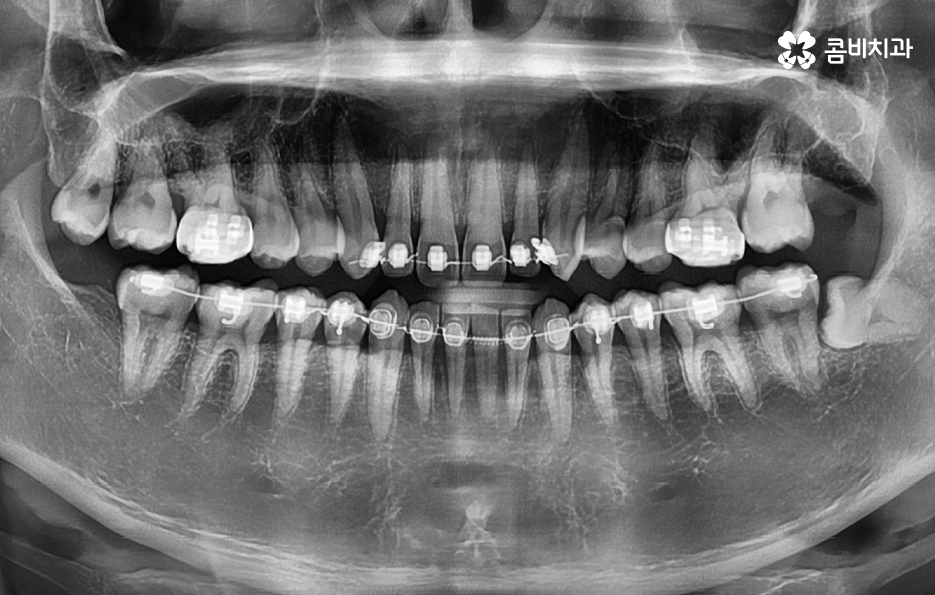

20살이 지났지만 사랑니가 안나고 있다고 생각하는 분들도 있지만 오히려 사랑니가 나올 공간이 부족하여 매복된 상태로 자라고 있는 경우가 많기 때문에 사랑니의 상태 체크를 위해 꼭 성인이 되신 분들은 사랑니의 확인을 위해서라도 꼭 검진을 받아보시길 바라며 매년 주기적으로 검진과 스케일링을 권하고 있는데요

현대인들은 사랑니의 위치가 좋지 않아서 주변 치아와 잇몸에 염증이 발생되는 사례가 많고 특히 하악에 매복 사랑니가 있는 경우가 많은데 완전히 누워서 자라는 사랑니는 발치 자체도 어렵지만 뿌리가 깊어지기 전에 발치하는 것이 발치나 회복에도 수월하기 때문에 정확한 사랑니 발치 시기의 골든타임을 놓치지 않기 위해서도 사랑니가 나올 무렵에 자신의 사랑니가 어떻게 자라고 있는지 확인하실 필요가 있어요

그리고 생각보다 많은 분들이 치아교정 전에 사랑니를 발치해야 하는지 궁금해 하시는 분들이 많은데 과거에는 교정 전에 꼭 충치 치료와 사랑니를 먼저 하고 치아교정을 진행했던 경우가 많았다고 할 수 있는데요

그 이유는 과거에는 교정은 교정 따로 사랑니 발치는 사랑니 발치 따로 치료가 진행되었던 경우가 많았기 때문에 지금처럼 협진이나 원스탑 진료 시스템이 잘 갖춰지지 않아서 교정 전에 사랑니 발치를 꼭 해야 했던 경우도 있었지만 현재는 각 개인의 상황에 따라서 교정 전에 하기도 하지만 교정 진행 중에 하기도 하고 교정이 끝난 후에 진행하는 경우도 있어요